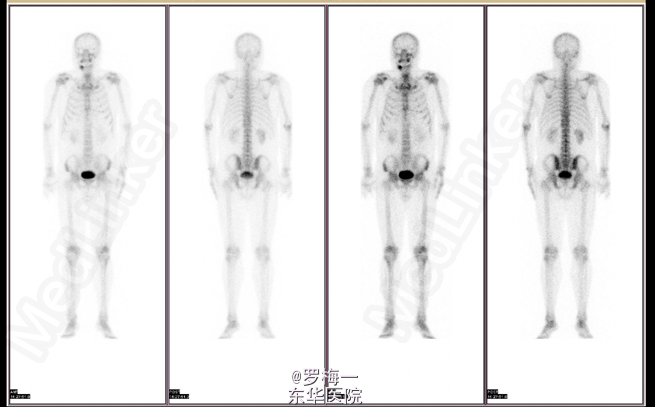

住院后完善相关检查,PSA两项均升高,其他各项术前常规检查未见明确手术禁忌证。遂于2015-04-02行经直肠前列腺穿刺活检,病理提示“符合前列腺增生伴慢性炎”。盆腔MR平扫+增强扫描考虑膀胱癌复发可能性大;彩超肝胆胰脾及核素骨扫描暂未见肿瘤远处转移证据。